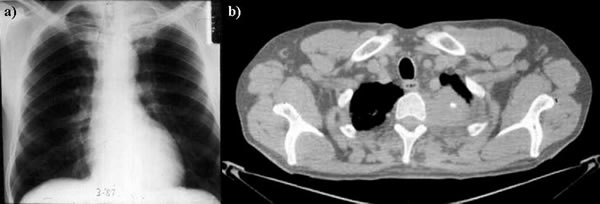

Медицина в деталях: Синдром Панкоста и диагностика